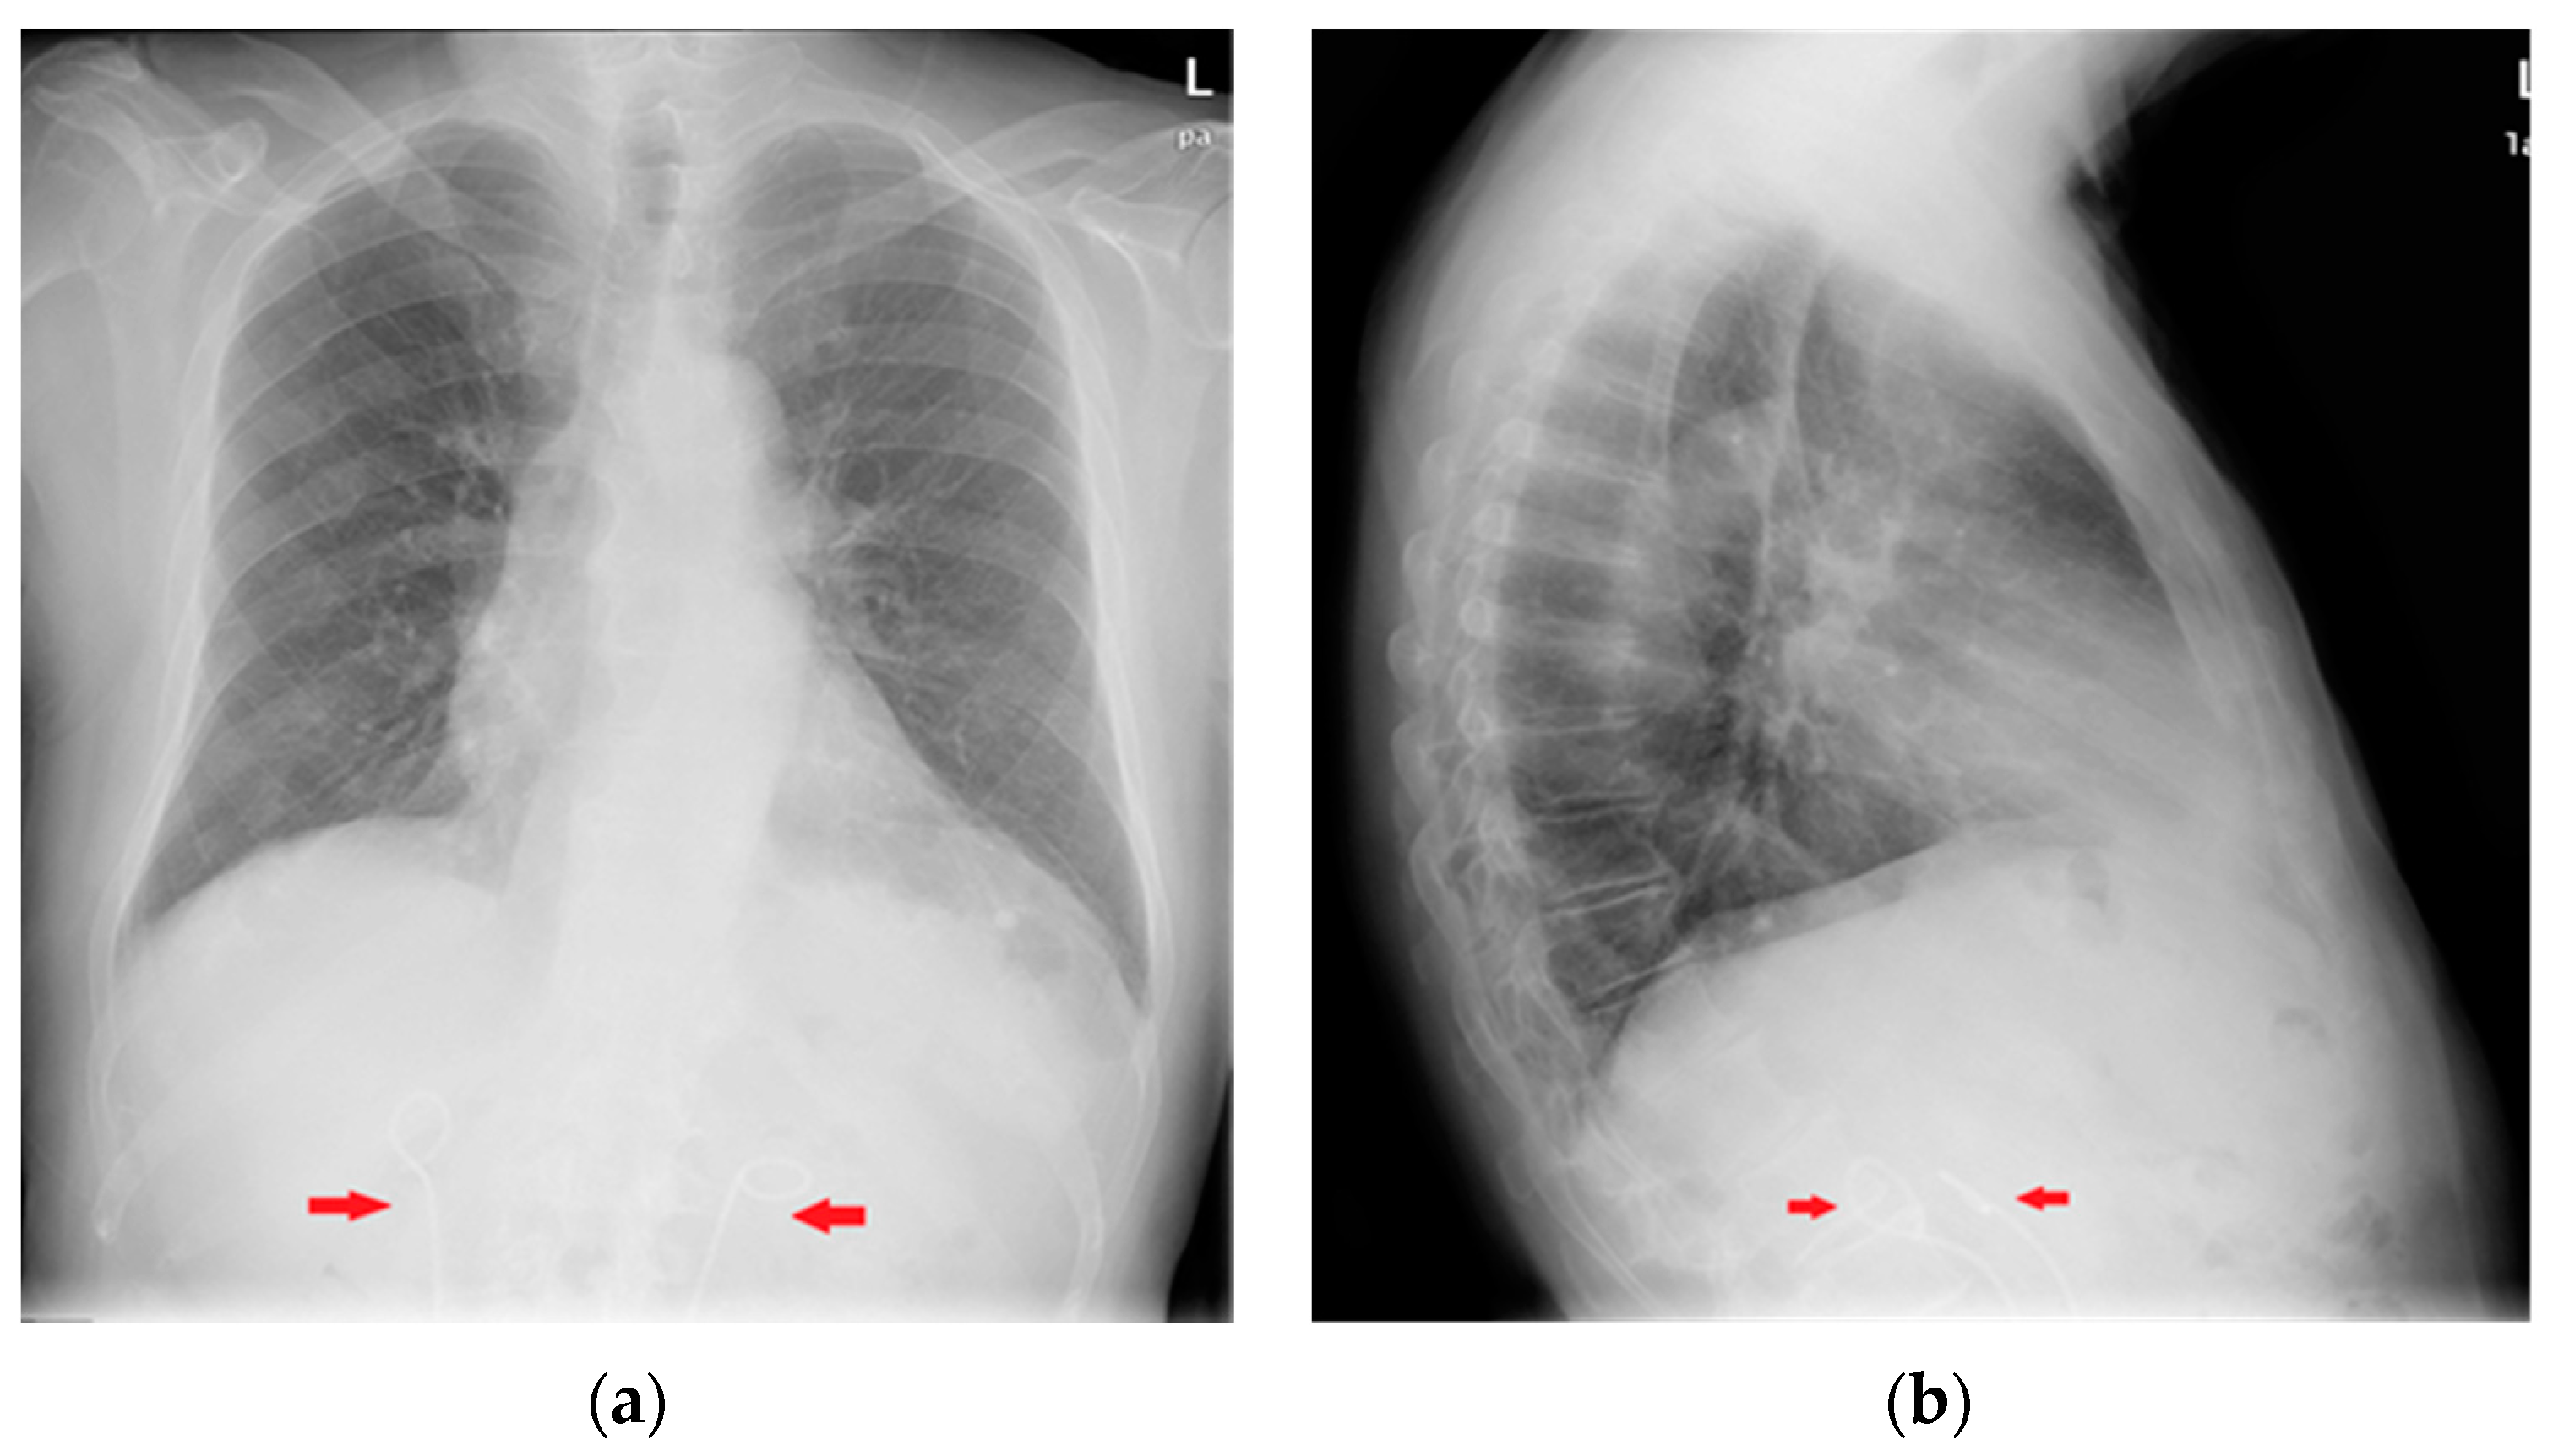

Figure 29.

Post-operative CXR illustrating two chest tubes with their tip in the right apical region. Note that whereas in the PA projection (a), the tubes seem to follow the same course, the LL view (b) clearly differentiates between an anterior and a posterior course.